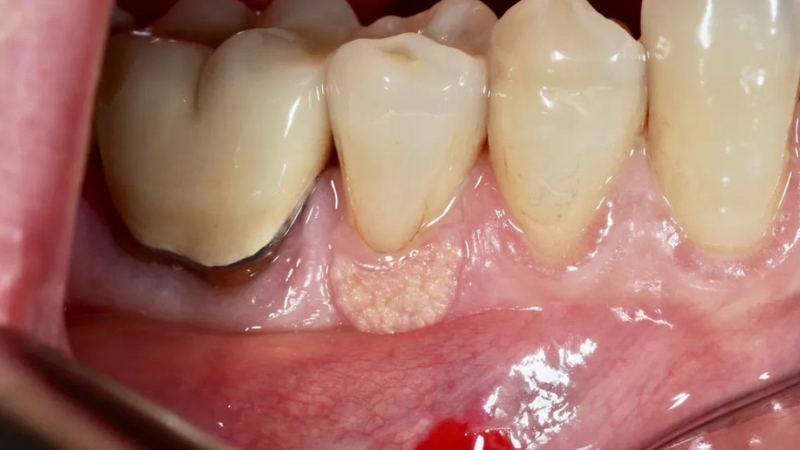

Có thể nhận biết sớm sùi mào gà ở nướu răng qua những dấu hiệu sau:

Sùi mào gà ở nướu răng tuy không gây đau cấp tính nhưng ẩn chứa nhiều nguy cơ nếu không được phát hiện và điều trị kịp thời. Ban đầu, các tổn thương u nhú có thể xuất hiện nhỏ lẻ và ít gây khó chịu. Tuy nhiên, nếu để kéo dài, chúng có xu hướng lan rộng nhanh, liên kết thành cụm lớn, gây chảy máu, nhiễm trùng và rất khó kiểm soát.

Với các tổn thương sùi mào gà ở nướu răng xuất hiện rõ, phương pháp điều trị tại chỗ thường được ưu tiên nhằm loại bỏ khối u nhú và giảm nguy cơ lây lan. Tùy vào mức độ tổn thương, bác sĩ có thể chỉ định đốt laser, áp lạnh (liệu pháp nitơ lỏng) hoặc sử dụng điện cao tần để phá hủy các mô bệnh.

Đốt laser CO₂ được đánh giá cao nhờ độ chính xác, ít gây chảy máu và giúp vùng tổn thương phục hồi nhanh nhưng chi phí điều trị khá cao. Áp lạnh là lựa chọn ít đau và thao tác nhanh, phù hợp với những tổn thương nhỏ, nhưng thường phải thực hiện nhiều lần mới đạt hiệu quả triệt để. Phẫu thuật cắt bỏ giúp loại bỏ hoàn toàn những tổn thương kích thước lớn, song có nhược điểm là dễ gây đau, chảy máu và cần gây tê trước khi tiến hành.